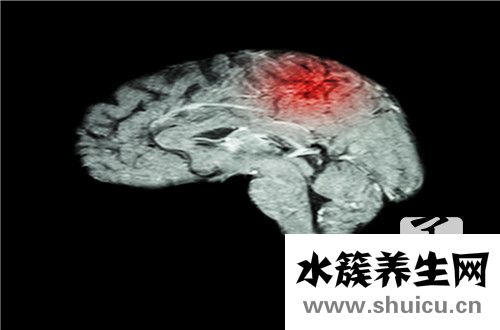

腦梗塞是中老年人的常見疾病。 它可能伴有許多疾病。 首先基本是頭暈,惡心或食欲不振的可能性。 因此,此類患者應引起重視。 飲食調整的關鍵是多吃粗糧,因為它很容易消化和吸收,所以要注意多吃水果,如...